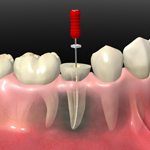

治療面では虫歯や歯周病、お子様の歯科治療などの一般、小児歯科、歯並びを健康的に改善する矯正治療、歯を白くキレイにする審美歯科・ホワイトニング、入れ歯に代わる自分の歯と同じ咬み心地のインプラント、軽度から重度の歯槽膿漏に対応できる歯周病治療などの幅広い診療をおこなっている歯科医院です。